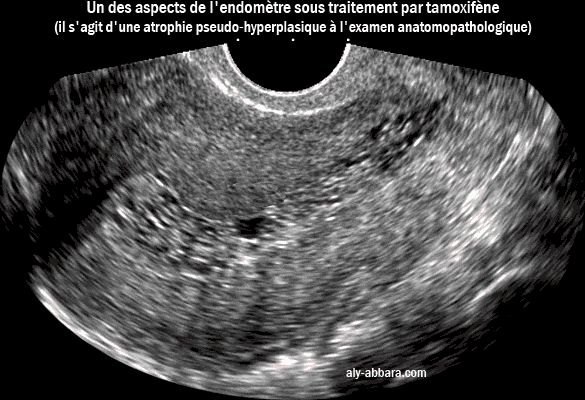

Un des aspects de l'endomètre sous traitement par tamoxifène, il s'agit d'une atrophie endométriale pseudo-hypertrophique

• Image échographique montant un des aspects de l'endomètre sous traitement par tamoxifène, il s'agit d'une atrophie endométriale pseudo-hyperplasique (résultats de l'examen anatomopathologique).

• L'endomètre sur cette image est de 12 mm d'épaisseur ; il est vacuolisé, c'est-à-dire formé de très nombreuses vacuoles disséminées dans l'ensemble de l'endomètre.

• Il s'agit d'une femme de 42 ans, traitée par tamoxifène (20 mg/j) depuis trois ans, dans le cadre de la prise en charge d'un cancer du sein découvert et traité depuis 4 ans. Suite à la radio-chimiothérapie, la patiente est en aménorrhée secondaire totale, sans aucune métrorragie.